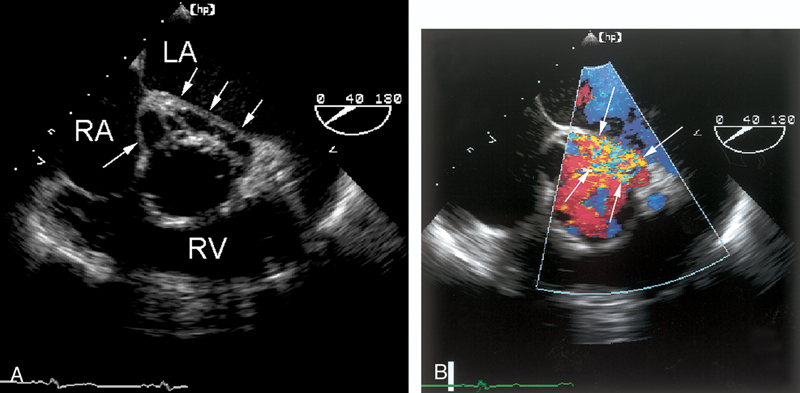

فحوصات تشخيصية لبعض امراض القلب والشرايين التاجية